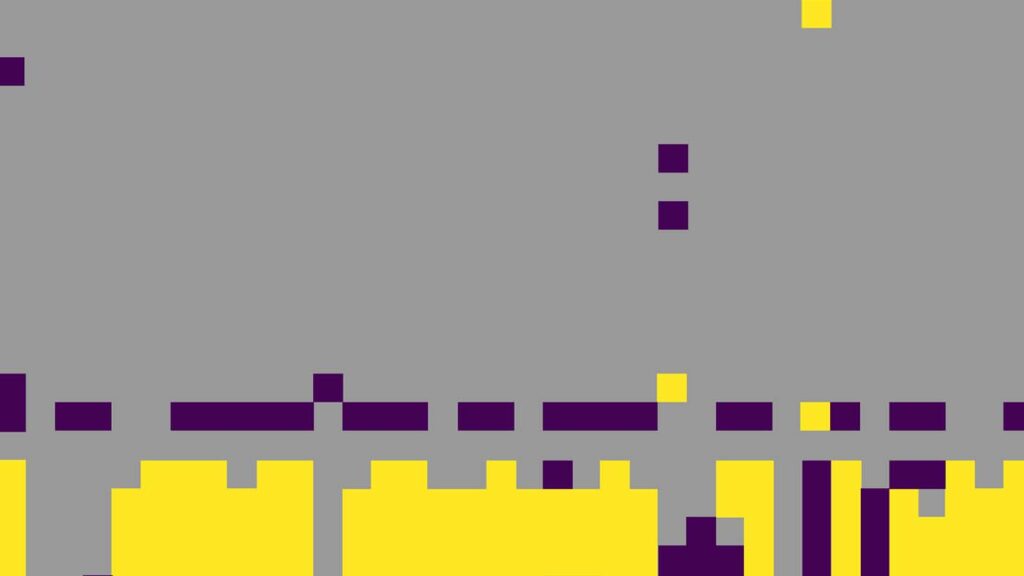

Sociodemographic and clinical features predictive of SARS-CoV-2 test positivity across healthcare visit-types